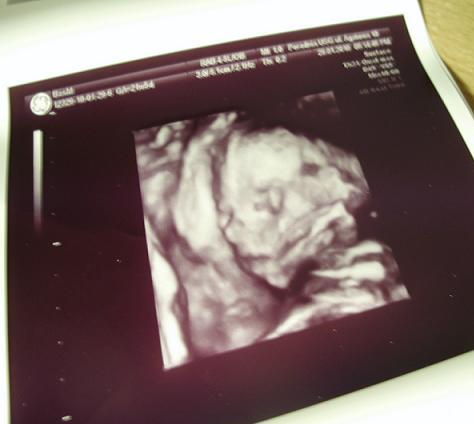

A to moja Nina :